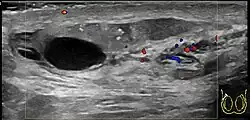

Epididymitis usually has a gradual onset. Typical findings are redness, warmth, and swelling of the scrotum, with tenderness behind the testicle, away from the middle (this is the normal position of the epididymis relative to the testicle). The cremasteric reflex (elevation of the testicle in response to stroking the upper inner thigh) remains normal.[1] This is a useful sign to distinguish it from testicular torsion. If there is pain relieved by elevation of the testicle, this is called Prehn's sign, which is, however, non-specific and is not useful for diagnosis.[13] Before the advent of sophisticated medical imaging techniques, surgical exploration was the standard of care. Today, Doppler ultrasound is a common test: it can demonstrate areas of blood flow and can distinguish clearly between epididymitis and torsion. However, as torsion and other sources of testicular pain can often be determined by palpation alone, some studies have suggested that the only real benefit of an ultrasound is to assure the person that they do not have testicular cancer.[14]: p.237 Nuclear testicular blood flow testing is rarely used.